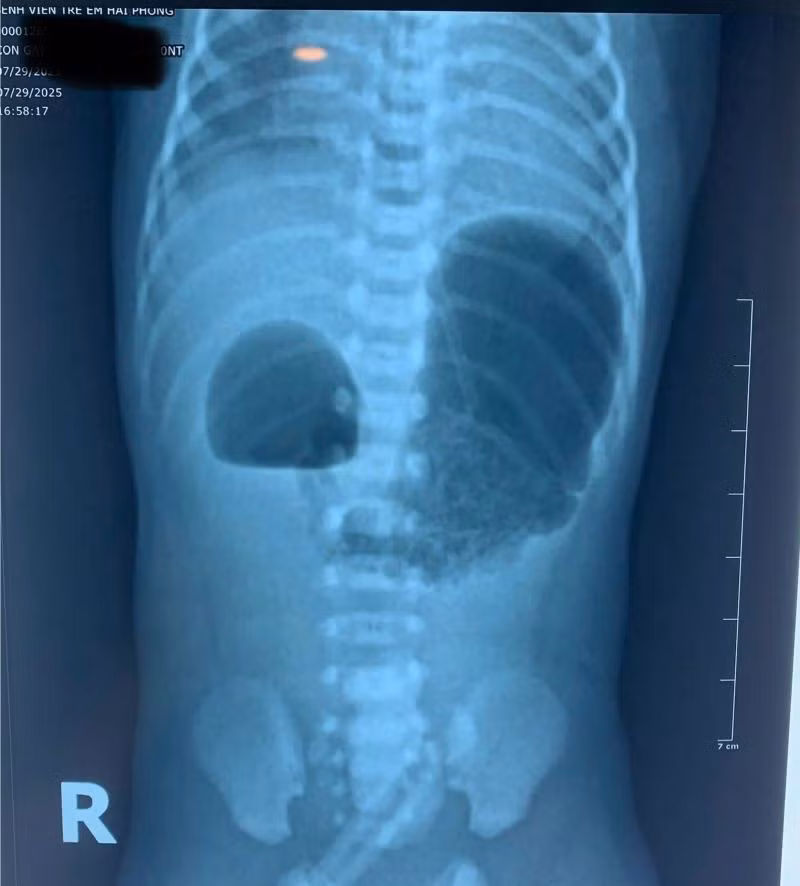

Hình ảnh tắc tá tràng bẩm sinh trên phim chụp - Ảnh BVCC

Khi nhập viện, bé ở trong tình trạng mất nước, thóp lõm, rối loạn điện giải và thiếu máu. Các bác sĩ đã nhanh chóng tiến hành hồi sức tích cực, nuôi dưỡng tĩnh mạch và bù điện giải, quá trình khám và làm các xét nghiệm chẩn đoán hình ảnh phát hiện trẻ bị tắc tá tràng bẩm sinh.